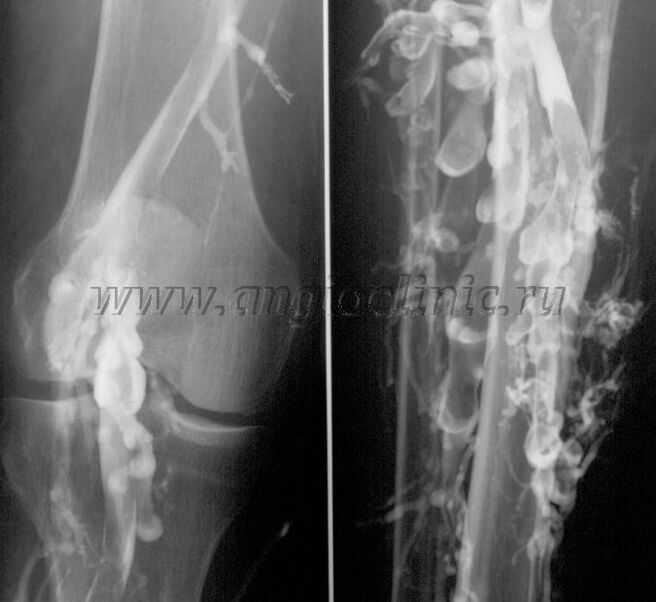

Contrast venography

Usually, an ultrasound scan is sufficient for a complete diagnosis of venous pathology, but in some cases it is necessary to study the relationship between the state of the deep and superficial venous system, especially in case of recurrent varicose veins and secondary varicose veins.

Contrast X-ray examination is used to solve these problems.The saphenous veins are punctured and contrast is administered.The movement of the contrast is observed on the X-ray machine screen and all necessary tests and projections are made.Currently, venography for varicose veins is used very rarely.